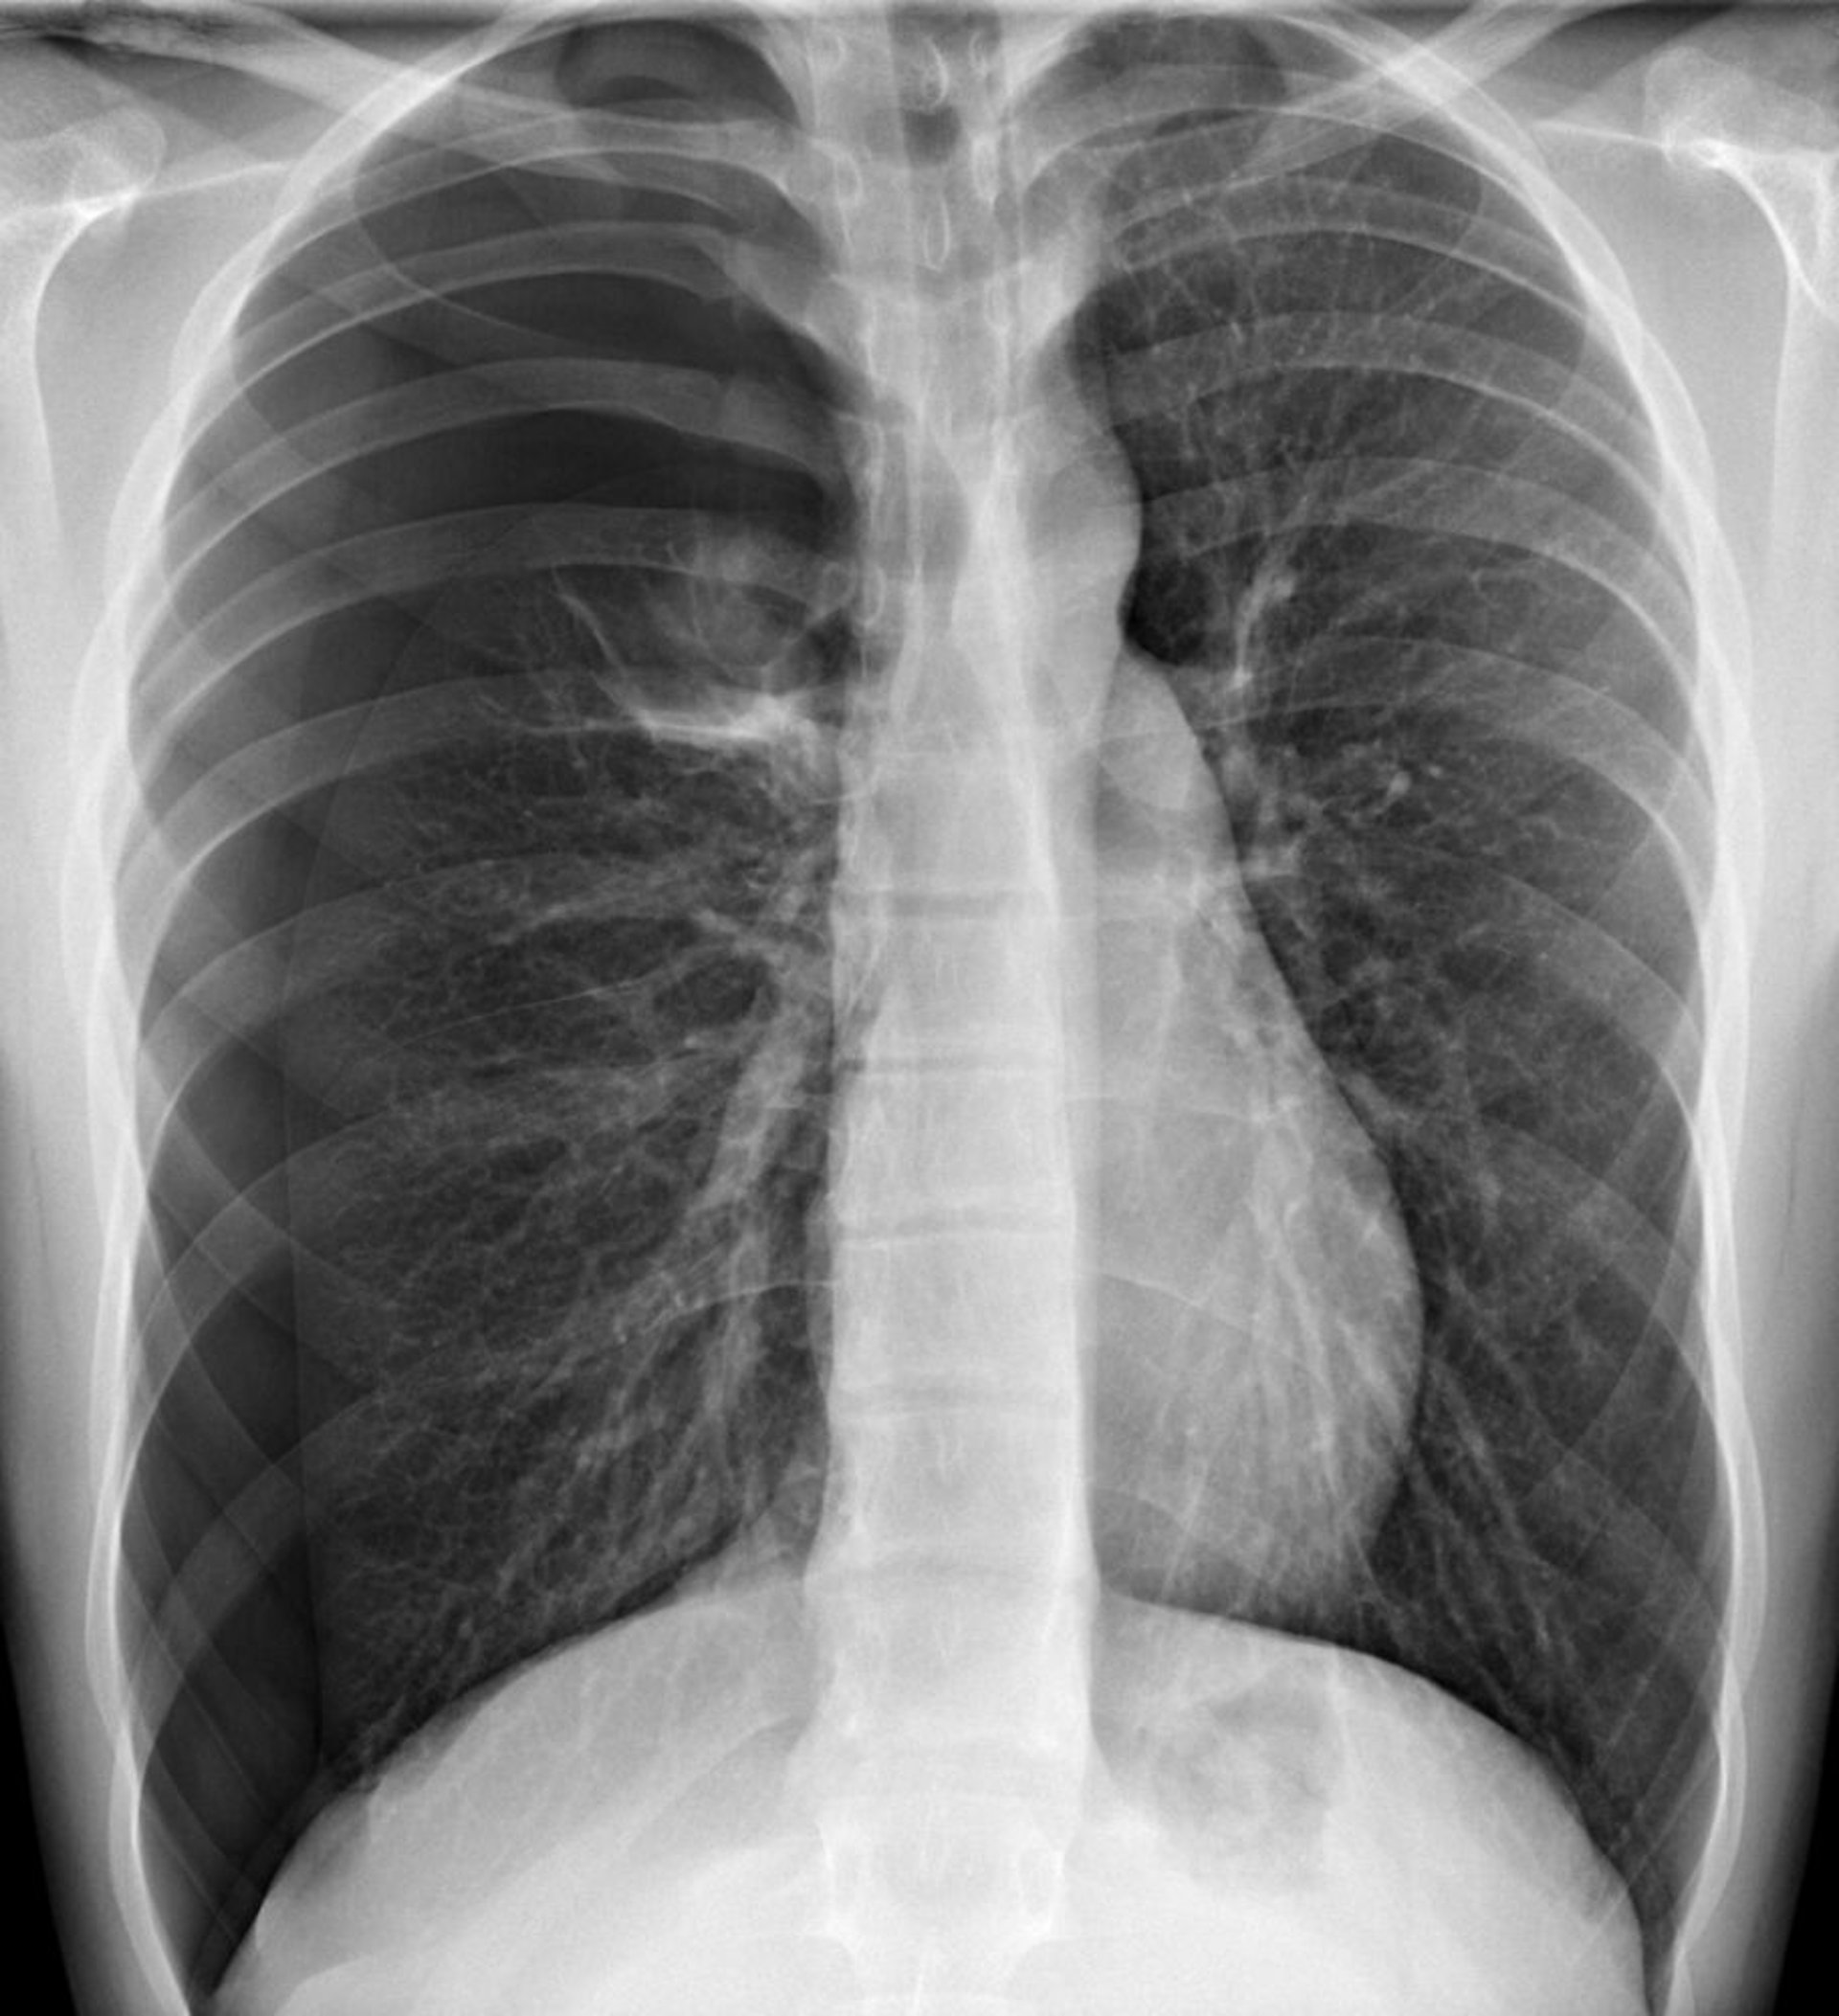

Pneumothorax compressif

Dans cette image, un pneumothorax est visible dans l'hémithorax droit, où, à la périphérie, il n'y a pas de marques pulmonaires. Un déplacement du cœur et du médiastin vers le côté gauche peut entraîner les effets physiologiques du pneumothorax compressif. Le pneumothorax compressif doit être diagnostiqué sur les signes cliniques.

DU CANE MEDICAL IMAGING LTD/SCIENCE PHOTO LIBRARY